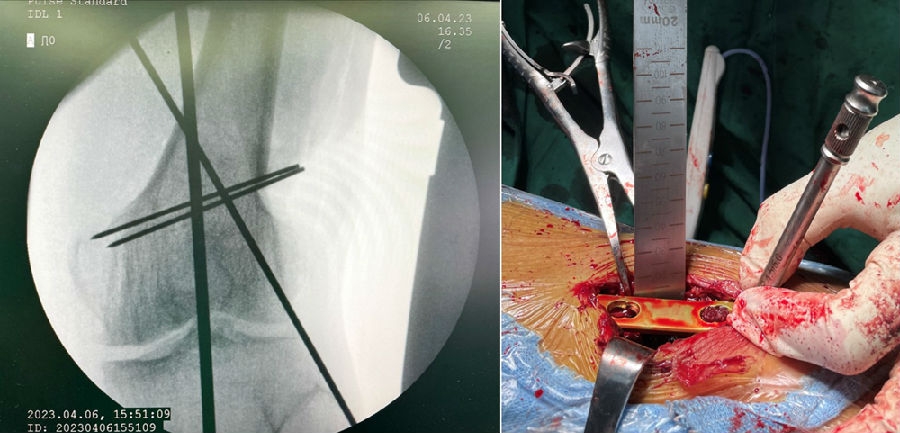

股骨胫骨双截骨的手术策略

1、手术方式

股骨畸形矫正:采用内侧闭合截骨或外侧闭合截骨。

胫骨畸形矫正:尽量采用内侧开放截骨术,部分特殊情况可以采用内侧闭合或外侧闭合楔形截骨术。

标准AO截骨课程

2、手术的顺序

对于手术顺序,提倡先做股骨。当股骨闭合,胫骨开放时,推荐优先做股骨,有利于准确调整下肢力线;当股骨闭合,胫骨闭合,同样推荐先做股骨,不容易发生相应的并发症。但是当出现术前全长片不标准,术前计划不准确时,建议先胫骨,胫骨较容易看关节线。

3、手术的关键

第一侧截骨要把关节线放平;第二侧截骨要达到整体目标力线。